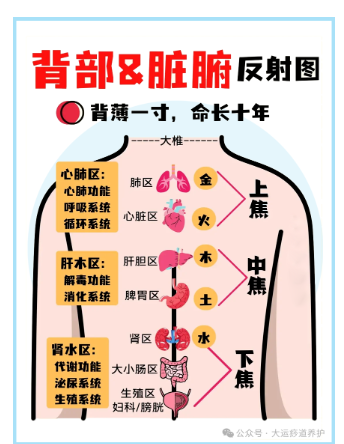

人体气血的圆运动是一个环环相扣的紧密系统,任何一脏的气都和他脏直接相关,如果一个环节出现寒凝淤堵,都会引起蝴蝶效应般的连锁反应,寒气如果长期在身体里周流,可见危害有多大。很多人并不知道自己到底是寒还是热,很多时候觉得自己寒,又有些时候觉得自己热,寒热的体验我们每个人都会有,五脏都有寒热之分。今天我们就一起来了解一下这方面的内容,看看心寒、肺寒、脾寒,肝寒、肾寒,各有什么表现,自己或身边的人出现症状时,可以明确知道自己更适合做哪方面的脏腑调理。心是君主之官,心寒了,身体就萎靡不振,做什么事都没有兴趣了。我们身体的阳气有两个来源,一个就是心阳,一个就是肾阳。心阳就好比太阳,心寒了就好比太阳失去了光芒,天空一片阴霾,大地一片死寂,万物将会凋零。如果心寒,面色就会苍白如雪,因为心,其华在面。嘴唇发青发紫,身上容易长很多斑,脸上、舌头上、手上、腿上都会长斑,因为心主血脉,各种斑斑点点就是血脉不通的表现。身上各种莫名其妙的淤青,稍微磕着碰着一大块淤青。心脏跳动缓慢,易导致大气下陷,时常叹气,总觉得胸闷、气短,总想深呼吸一口气,遇冷则心痛发作。心寒了,还会出冷汗,因为汗为心之液,心阳不足就无法固摄汗液,汗就容易出来。心寒的人,无欲无求,无所事事,碌碌无为,做什么都觉得没有意思,也几乎没有什么欲望了,有时候,甚至连食欲也没了。所以抑郁症的人一定要从心上调理,强 壮他们的心阳,驱除他们心中的刺骨寒意。肺是相傅之官,肺朝百脉,肺就像宰相,是一人之下万人之上,肺寒了,这座连接心与百脉的桥梁就会垮掉,肺寒了,全身经络就会堵塞。肺寒就会流清鼻涕,稍微着点凉,鼻涕像清水一样流下来。特别容易风寒感冒,因为卫气不足。没有阳气化开肺中的水液,就会凝结成痰,这样的痰颜色是白的,会不停地吐痰。容易不停地咳喘,这种咳喘夜间严重,有很多白痰,秋冬容易发作。肺寒者必气虚,身体总觉得没劲,没力气干活,老想躺着,因为肺主一身之气。肺寒的人不太容易出汗,因为肺主皮毛,肺的宣发能力不够出汗就很少,即使是夏天也很少出汗。肺寒者,还可能会便秘,是那种大便不硬,排便吃力,大便比较细的便秘。肺寒之人一定不要喝冷饮,形寒饮冷则伤肺。脾得温则运化,脾寒了就运化不起来,脾胃是五脏六腑的中心,脾胃不运化整个身体都会出问题。很多人都有胃强脾弱的毛病,吃啥都拉肚子,完谷不化,其中一个重要的原因就是脾寒了。脾喜欢温,不喜欢寒凉。如果脾寒了,就会有很多湿气,因为脾为湿气之源,脾寒不运化,湿邪就会停留身体,泛滥成灾。所以祛湿一定要温脾、健脾。脾寒了,面色就会萎黄,吃东西会积食,就算吃的不多也运化不了,堆在身体就会积食,就会发胖。脾寒,要么很多口水,总是吐不完,睡觉口水流下来,要么就是口干,但是喝水又不解渴。经常会腹泻,吃点生冷寒凉就要拉肚子。会容易感到腹胀,下午表现尤为明显,因为下午的阳气渐渐衰弱。脾主肌肉,脾寒的人常年四肢无力,严重的人还会得重症肌无力。肝是将军之官。肝体阴而用阳,阳气是很足的,所以我们常常说肝火大,很少说肝受寒了。肝一般是不受寒的,一旦受寒,就比较严重。肝寒,可能会腹痛,这种腹痛不是肠道的问题,其实就是肝经经过的地方堵住了,是一种隐隐作痛。比较容易出现关节冷痛,其实并不是骨头出了问题,而是维系关节间的筋出了问题。如果说心阳就像天上的太阳,那么肾阳就是潜藏在地壳深处的热能。

肾藏精,这个精化成两股力量,一股叫肾阴,一股叫肾阳。肾寒,首先表现在全身怕冷,不仅仅是手脚冰凉,冬天很难过,夏天很舒服,平常穿衣服比一般人要多很多。会经常腰痛,是那种冷痛的感觉,腰部特别怕冷风吹,用热水袋捂一下舒服很多,因为腰为肾之府。肾寒者会尿频,这种尿频不是那种每次尿很少每次一点点很快又有尿意的那种,而是尿很多,清晰如水,尤其夜尿多。因为肾司二便。同理,还会五更泻,就是早上五点左右起来腹泻。肾寒者比较容易水肿,尤其是腰以下水肿,因为膀胱里面的水液需要肾阳的气化才能被利用或者排泄。很多慢性肾炎的人都是脾肾阳虚。五脏有寒气,可以靠中医艾灸,进行脏腑调理,驱赶寒气。万病从寒起,守护一身正气,寒邪勿犯,才能靠近养生的最终目的“形与神倶”。